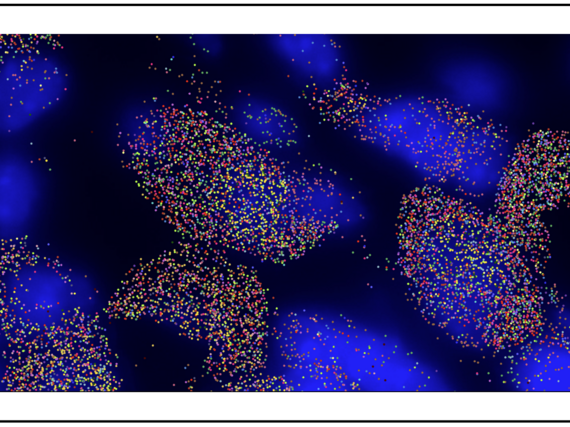

Mechanismus zur Behandlung von Muskelschwund entdeckt

Utrophin-Anstieg in Muskelzellen nach transkriptionaler Adaptation normalisiert Zellfunktion bei Duchenne Muskeldystrophie